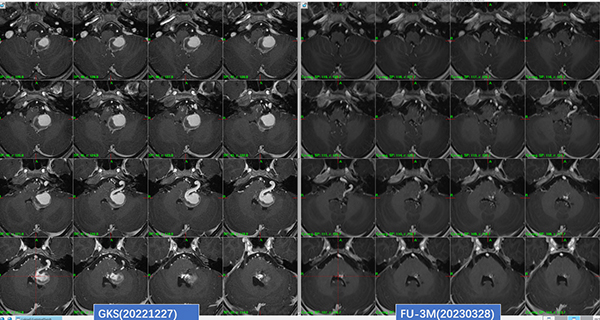

图:6岁脑干动静脉畸形,DSA+MR联合精准定位AVM,3月患儿症状明显改善,影像可见巨大静脉球消失,畸形团缩小,静脉梗阻性水肿消失